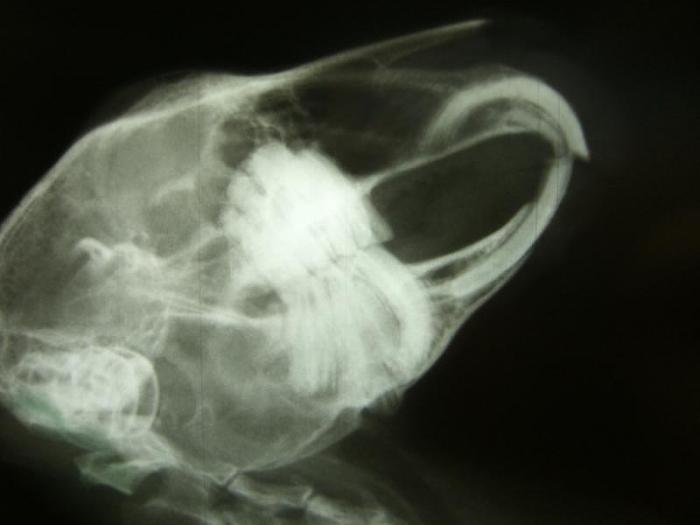

Und sie hat nicht nur mich voll unvorteilhaft geknipst, neeeeeeee sie tut Euch auch noch meinen Kopf von innen zeigen. Ganz schön krumm und schief bin ichNur mein Bauch und mein Herz sieht toll aus